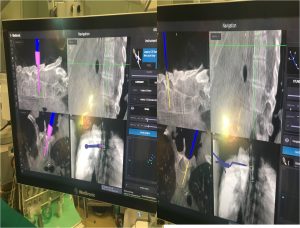

Εικόνα 2 : Οθόνη στην οποία παρακολουθείται από το σύστημα πλοήγησης σε πραγματικό χρόνο η πορεία της διαυχενικής βίδας μέσω του μίσχου (pedicle) εντός του σπονδυλικού σώματος.